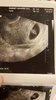

received_313534982795138.jpeg

• received_313534982795138.jpeg

79,5 KB · Wyświetleń: 348